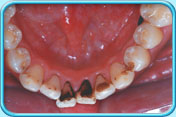

牙齒表面有啡黑色漬

有黑色漬的牙齒原因

經常飲用深色的飲品如茶等,色素就會沉積在牙齒表面。